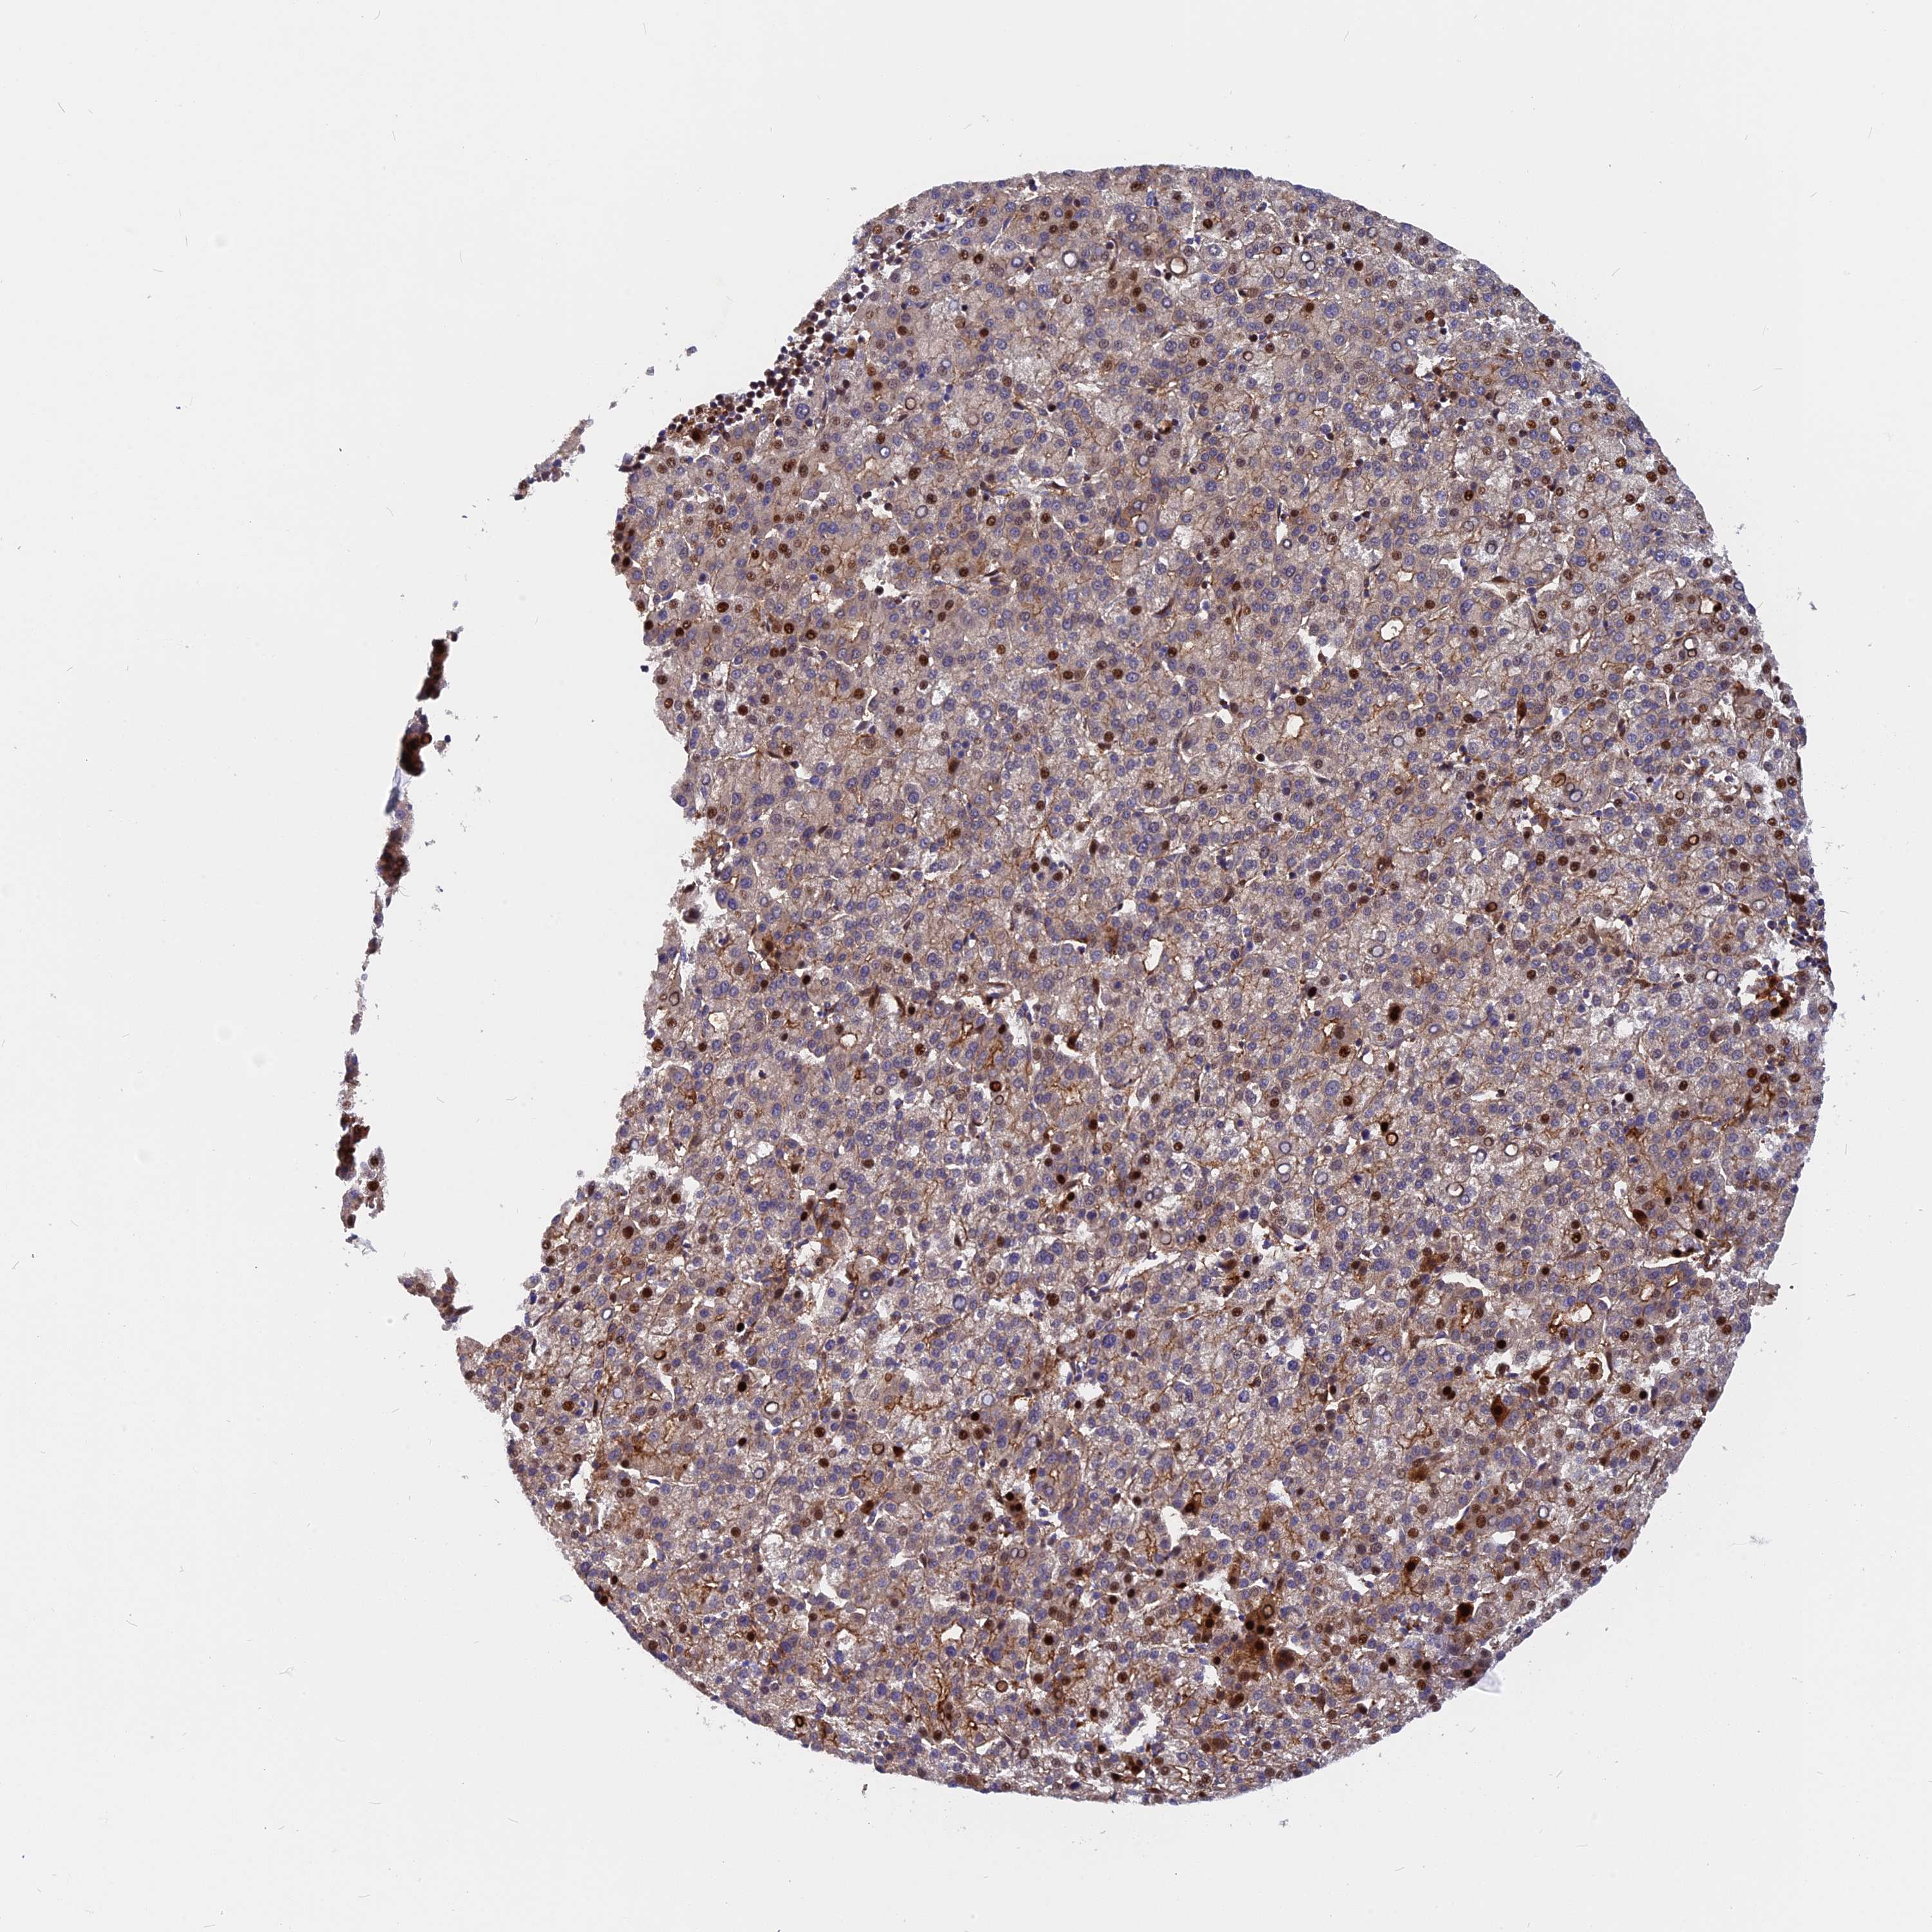

LIVER CANCER - Protein expressioni

A mouse-over function shows sample information and annotation data. Click on an image to view it in a full screen mode. Samples can be filtered based on level of antibody staining by selecting one or several of the following categories: high, medium, low and not detected. The assay and annotation is described here.

Note that samples used for immunohistochemistry by the Human Protein Atlas do not correspond to samples in the TCGA dataset.

Antibody stainingi

Antibody staining in the annotated cell types in the current human tissue is reported as not detected, low, medium, or high, based on conventional immunohistochemistry profiling in selected tissues. This score is based on the combination of the staining intensity and fraction of stained cells.

Each image is clickable and will lead to virtual microscopy that enables deeper exploration of all samples and also displays staining intensity scores, fraction scores and subcellular localization as well as patient and tissue information for each sample.

Antibody HPA043339

Staining

High

Medium

Low

Not detected

Intensity

Strong

Moderate

Weak

Negative

Quantity

>75%

75%-25%

<25%

None

Location

Nuclear

Cytoplasmic/membranous

Cytoplasmic/membranous,nuclear

Cholangiocarcinoma

Carcinoma, Hepatocellular, NOS